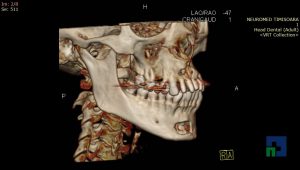

- Diagnosticul fracturilor:

- Unice

- Multiple

- Cu înfundare

- Complexe cranio-sinusale

- Complexe cranio-etmoidale

- Complexe cranio-orbitare

- Complexe cranio-faciale